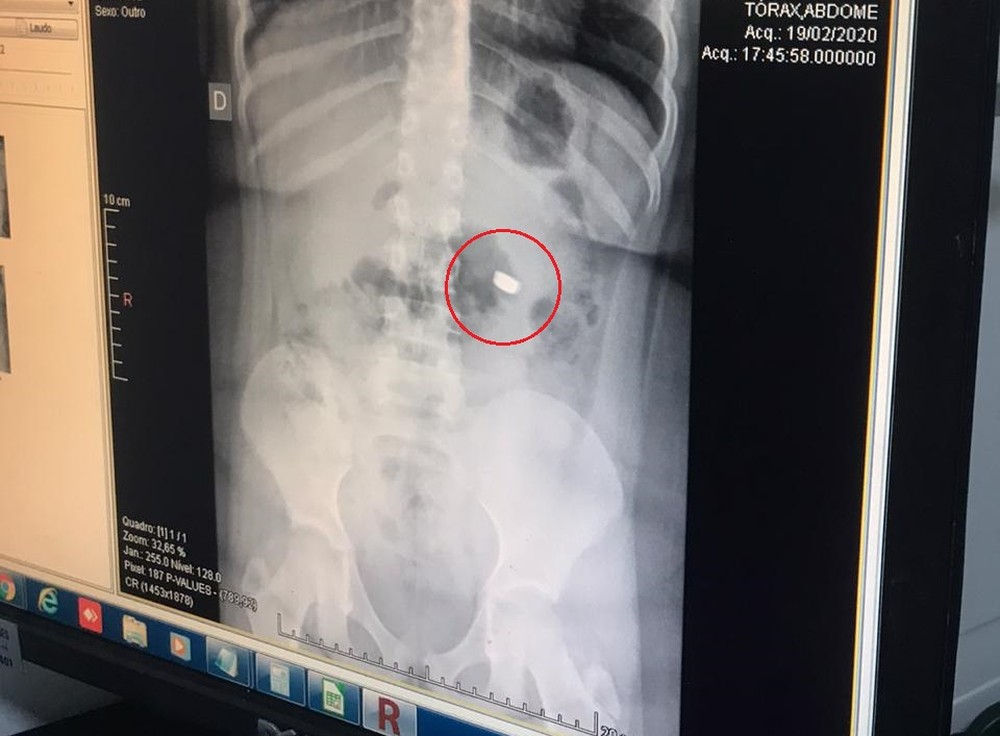

Criança é internada após engolir bateria de lanterna